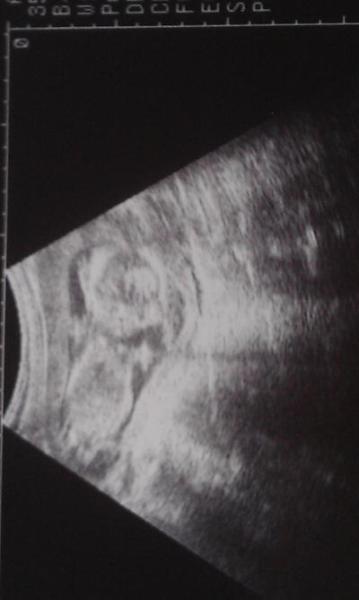

Zwar nicht so toll,weil unsere Hummel heute im wahrsten Sinne Hummel im hintern hatte....aber alles prima und von 15+6 auf 16+2 gerutscht Und leider kein outing...und wieder abgenommen....:(

Bild zu wieder zurück... - Forum für August - Mamis